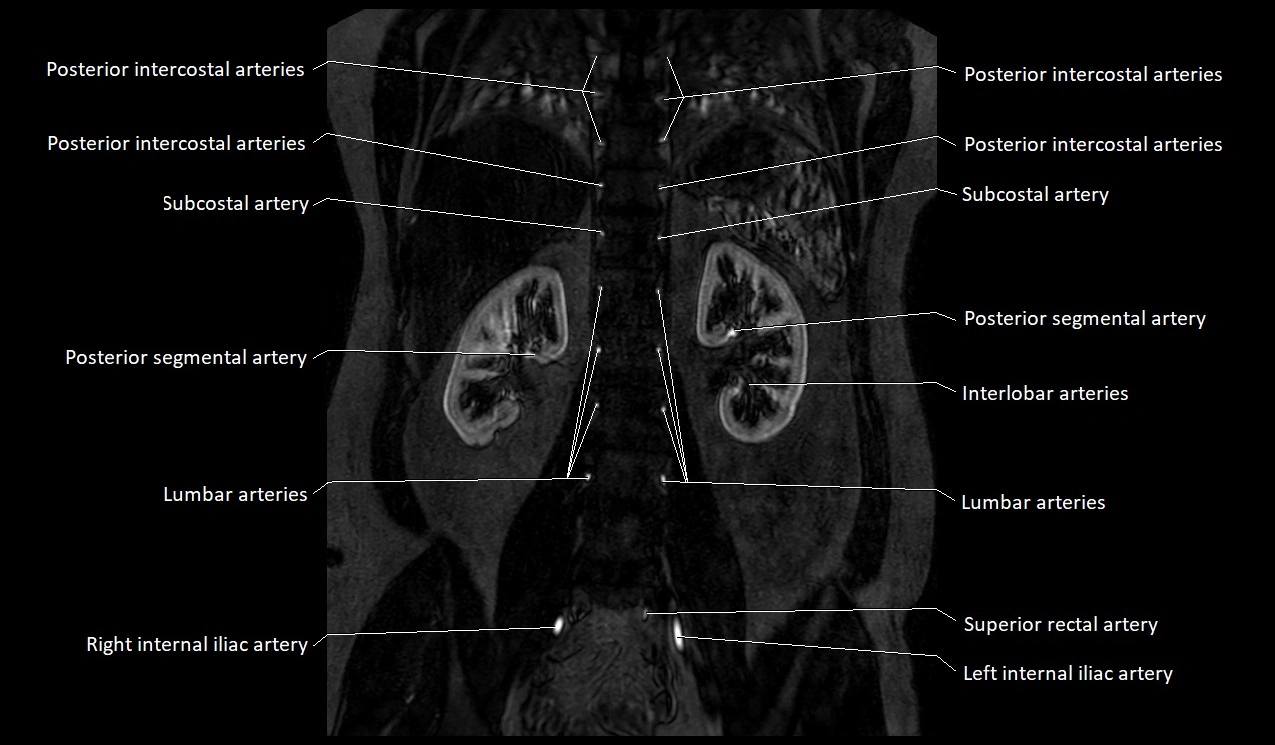

MRI Appearance

T1-weighted images:

Artery appears as a small linear hypointense flow void coursing over the superior pubic ramus

Seen within bright perivascular fat of pelvis

MRA Pelvis with Gadolinium:

Clearly delineates the origin, course, and anastomoses of the accessory obturator artery

Identifies connection with inferior epigastric artery, external iliac artery, or obturator artery

Excellent for detecting vascular variants prior to surgery

Useful in mapping pelvic vasculature in trauma, tumor embolization, or preoperative planning